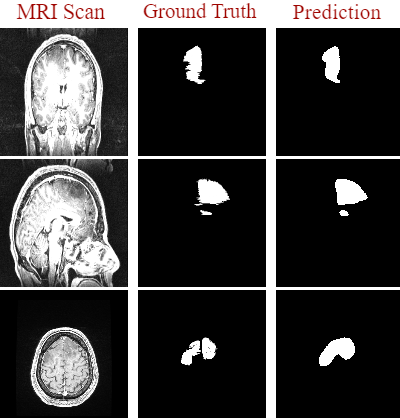

Magnetic Resonance Imaging (MRI) is the most commonly used non-intrusive technique for medical image acquisition. Brain tumor segmentation is the process of algorithmically identifying tumors in brain MRI scans. While many approaches have been proposed in the literature for brain tumor segmentation, this paper proposes a lightweight implementation of U-Net. Apart from providing real-time segmentation of MRI scans, the proposed architecture does not need large amount of data to train the proposed lightweight U-Net. Moreover, no additional data augmentation step is required. The lightweight U-Net shows very promising results on BITE dataset and it achieves a mean intersection-over-union (IoU) of 89% while outperforming the standard benchmark algorithms. Additionally, this work demonstrates an effective use of the three perspective planes, instead of the original three-dimensional volumetric images, for simplified brain tumor segmentation.

翻译:磁共振成像(MRI)是最常用的医学图象获取非侵入性技术。脑肿瘤分解是大脑MRI扫描中算法识别肿瘤的过程。虽然文献中为脑肿瘤分解提出了许多方法,但本文建议对 U-Net 进行轻量应用。除了提供MRI 扫描的实时分解外,拟议的结构不需要大量数据来培训拟议的轻量U-Net。此外,不需要额外的数据增强步骤。轻量U-Net显示BITE数据集非常有希望的结果,它取得了89 % 的平均交叉连接(IOU), 并且超过了标准基准算法。此外,这项工作表明,在简化脑肿瘤分解方面,有效使用了三种视角平面, 而不是原来的三维体量图。